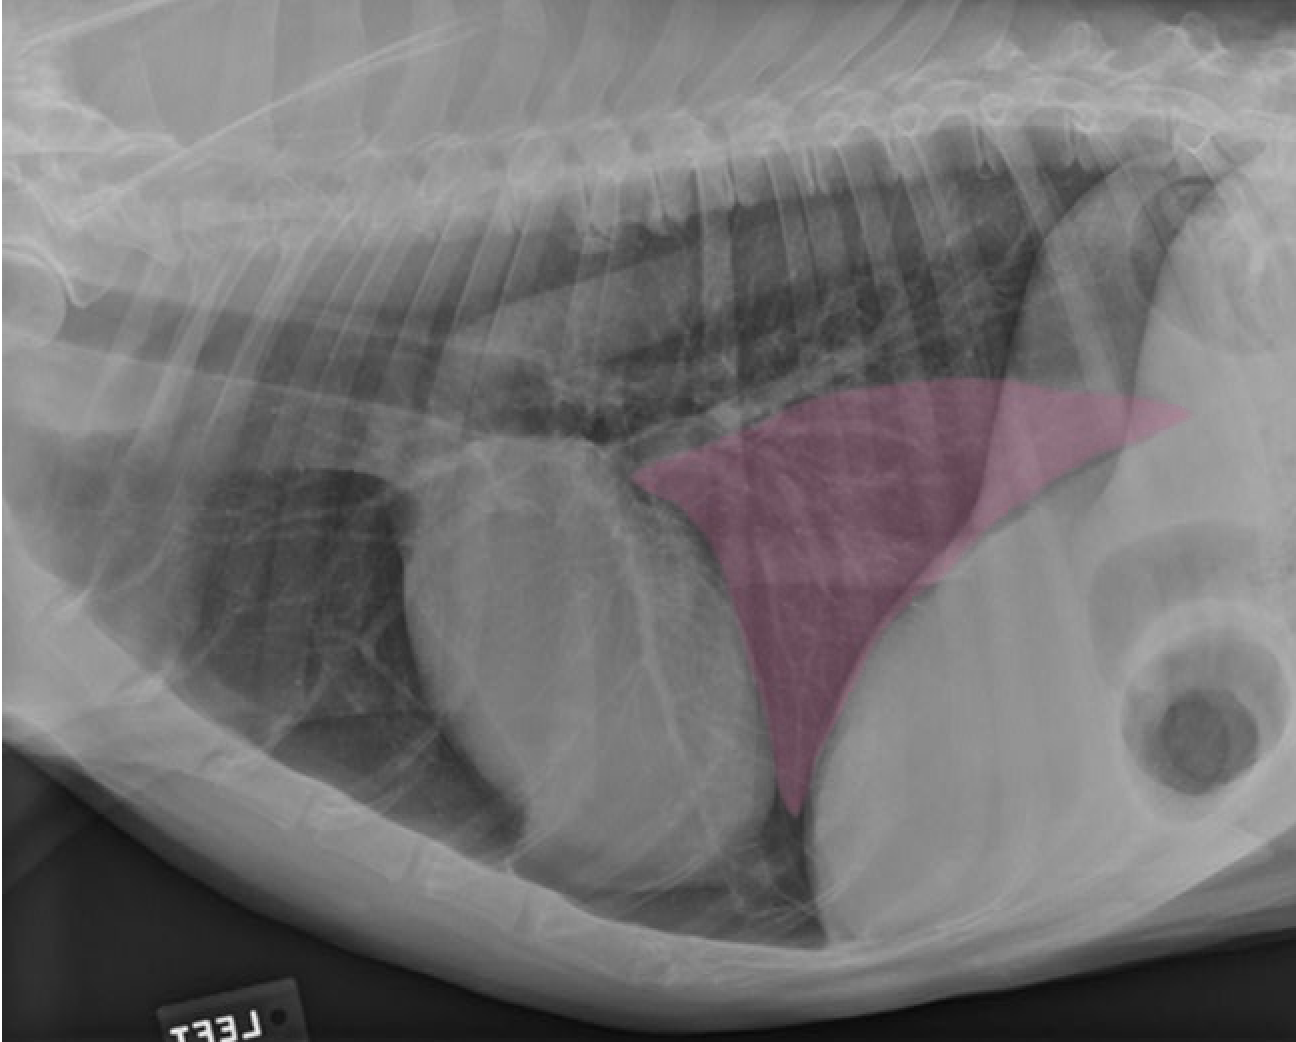

identify the structures

identify the pulomary arteries

identify the aorta

identify the ventral mediastiunum

identify the scapula

identify the ventral lung lobes